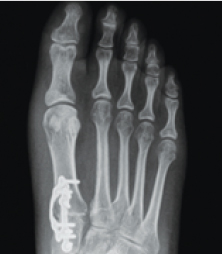

Instead of cutting the bone in half and shifting the top part over, the patented Lapiplasty® Procedure uses specially-designed instrumentation to rotate the entire deviated bone back into its normal anatomical position, naturally straightening your toe; removing the "bump" and associated pain. Innovative titanium plating technology5,6 permanently secures the unstable foundation, the root of your bunion problem. Most patients are able to walk within days of surgery.1 No cast is required; allowing patients to get back to the shoe wear of their choice and activities quickly.1

The Lapiplasty® Procedure utilizes two low-profile (petite), anatomically-shaped titanium plates to permanently secure the unstable foundation of your corrected bunion. This provides buttressing on multiple planes and allows you to walk within days of surgery.1 Think of this in terms of how a basketball player might hold a basketball. When a player tightly grips the ball with both hands, the ball is held more securely than if only one hand is used.

Unlike other surgical approaches, the Lapiplasty® Procedure utilizes two plates for this very reason – "Two plates are better than one".7